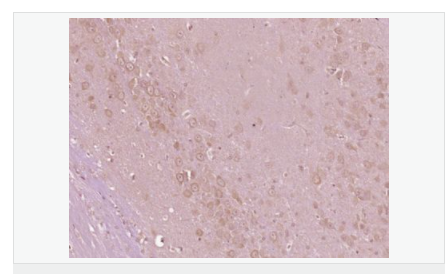

產(chǎn)品應(yīng)用ELISA=1:5000-10000 IHC-P=1:100-500 IHC-F=1:100-500 IF=1:100-500 (石蠟切片需做抗原修復(fù))

Most abundant in the brain, with highest levels in amygdala and hippocampus. Low levels in kidney (at protein level). Also expressed in spleen and lymphocytes.

富含脯氨酸的酪氨酸激酶 2 (protein richtyro sinekinase 2 ,PYK2 ) ,又稱細(xì)胞粘附激酶β(cellularadhesionkinaseβ ,CAKβ)、相關(guān)粘附聚焦酪氨酸激酶(relatedadhesionfocaltyrosinekinase ,RAFTK) ,是粘著斑激酶 (focaladhesionkinase,FAK)家族的成員之一。PYK2是FAK家族的成員之一 ,是一種鈣依賴性酪氨酸激酶 ,在氨基酸序列上與FAK有 4 5 %的同源性。它的活化涉及了多條信號(hào)傳導(dǎo)通路 ,與離子通道的調(diào)節(jié)、細(xì)胞骨架的聯(lián)系及細(xì)胞增殖、凋亡密切相關(guān)。血管緊張素Ⅱ、一氧化氮可調(diào)節(jié)PYK2的活性。在神經(jīng)系統(tǒng)中高度表達(dá)的蛋白酪氨酸激酶 (Pyk2),其酪氨酸殘基因?yàn)楦鞣NG蛋白偶聯(lián)受體和胞外信號(hào)而被磷酸化,從而增加胞內(nèi)鈣離子的濃度.